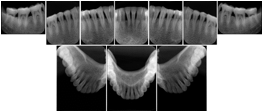

2 Occlusal Vertical Maxilla A Dental Image Layout

DL-C001A

Reference: DL-C001-U1L0

Reference: DL-C001-U2L0

2 Occlusal Vertical Mandible A Dental Image Layout

DL-C002A

Reference: DL-C002-U0L1

Reference: DL-C002A-U0L2

2 Occlusal Horizontal Maxilla A Dental Image Layout

DL-C003A

Reference: DL-C003-U1L0

Reference: DL-C003-U2L0

2 Occlusal Horizontal Mandible A Dental Image Layout

DL-C004A

Reference: DL-C004-U0L1

Reference: DL-C004-U0L2